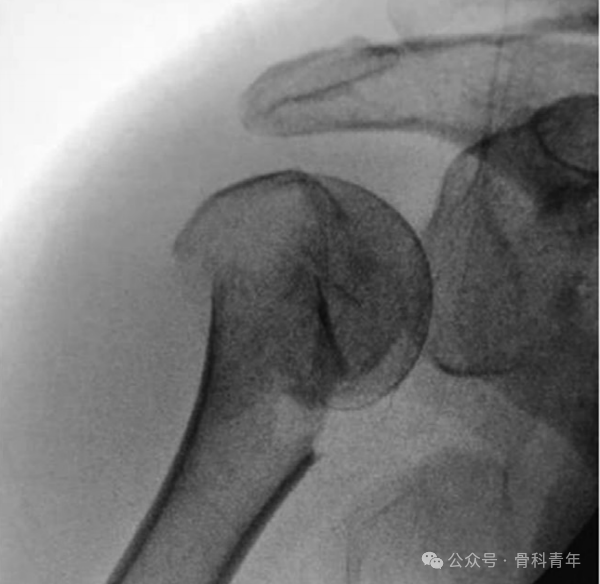

钢板螺钉系统是目前最常用的肱骨近端内固定系统,但对老龄骨质疏松性骨折,肱骨头内部的支撑不足仍是临床需面对的问题,各种解决方案,如骨水泥填充、植骨填充、球囊扩张、腓骨填充等,应用于临床。国外学者在《Journal of orthopaedic science》介绍了一种低切迹钢板联合“钉中钉技术”固定的方法,旨在解决此问题,供临床医生参考。